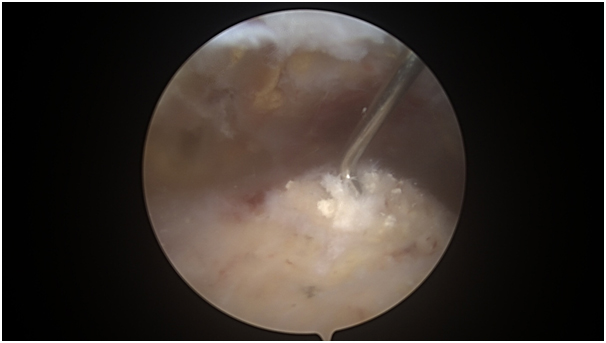

Η χειρουργική θεραπεία χρόνιου ασβεστοποιού τενοντίτιδας ώμου γίνεται ελάχιστα-επεμβατικά, με τη χρήση μιας ειδικής κάμερας και λεπτών εργαλείων που προωθούνται μέσα από πολύ μικρές τομές που ανοίγει ο χειρουργός στο δέρμα του/της ασθενούς. Η επέμβαση αυτή καλείται αρθροσκόπηση ώμου.

Η αρθροσκόπηση ώμου είναι μια ελάχιστα-επεμβατική τεχνική στην οποία ο εξειδικευμένος Ορθοπαιδικός Χειρουργός χρησιμοποιεί ένα αρθροσκόπιο (ειδική μίνι κάμερα) για να εξετάσει το εσωτερικό της άρθρωσης του ώμου. Ορισμένες παθήσεις του ώμου μπορούν να θεραπευτούν αρθροσκοπικά. Σε αυτές τις περιπτώσεις, για να πραγματοποιήσει την επέμβαση, ο χειρουργός κάνει μικρές τομές (σαν κλειδαρότρυπες) για να δημιουργήσει τα σημεία πρόσβασης από τα οποία θα εισάγει στην άρθρωση του ώμου, τα λεπτά χειρουργικά εργαλεία και την κάμερα.

Στην περίπτωση της εμμένουσας ασβεστοποιού τενοντίτιδας του ώμου, ο στόχος της αρθροσκοπικής επεμβατικής θεραπείας είναι να εξαλειφθεί το γενεσιουργό αίτιο του πόνου (ο βράχος μέσα στον τένοντα), αλλά και να καθαριστεί η φλεγμονή του θυλάκου και του τένοντα. Η αρθροσκοπική τεχνική θεραπείας της εμμένουσας ασβεστοποιού τενοντίτιδας του ώμου περιλαμβάνει την έκπλυση και πλήρη αφαίρεση της ασβέστωσης από το εσωτερικό του τένοντα. Στην περίπτωση μεγάλης ασβέστωσης, το κενό που μένει εντός του τένοντα μετά την αφαίρεση της ασβέστωσης (του βράχου), συγκλείεται με ένα ειδικό αρθροσκοπικό ράμμα (μινι ράμμα).

Πέραν τούτου, επιπρόσθετες χειρουργικές πράξεις που συχνά πραγματοποιούνται στα πλαίσια της εν λόγω επέμβασης, με τη χρήση κάμερας, είναι 1) ο καθαρισμός του υπακρωμιακού θυλάκου (θυλακεκτομή) που καλύπτει τους τένοντες του στροφικού πετάλου και, συχνά, φλεγμαίνει, 2) ο καθαρισμός της φλεγμονής των τενόντων του στροφικού πετάλου με ειδικό αρθροσκοπικό εργαλείο (shaver) που νεαροποιεί τον εκφυλισμένο τενόντιο ιστό, 3) η πραγματοποίηση τενοντοτομής (ή τενονοντόδεσης) της μακράς κεφαλής του δικέφαλου βραχιονίου και, 4) ακρωμιοπλαστική.